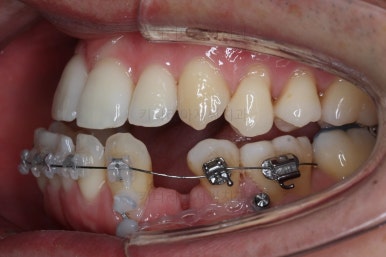

어느 정도 진행이 되었다 싶으면 윗니도 장치를 부착해서 가지런하게 해줘요.

윗니도 장치를 부착했어요.

아랫니보다 해야 할 작업이 많지 않기 때문에 이렇게 시간차를 두어 진행을 했고, 이렇게 하면 교정장치가 눈에 띄는 기간이 줄어들어 환자분의 만족도는 더 올라가게 되죠.

아랫니 이 뽑은 자리는 거의 다 다물렸어요.

거꾸로 물리는 앞니도 어느 정도 많이 개선이 되었고요.

이 정도 진행되면 입매에 대해서 평가를 합니다.

아랫입술이 상당히 많이 들어갔죠? 치료의 목표가 턱뼈를 짧게 만드는 것도 아니고 교합을 맞춰주는 것인데 치료를 하다보면 얼굴모습도 좋아져요.

거꾸로 물리던 아래 앞니가 뒤로 들어가면서 튀어나왔던 아래입술이 뒤로 들어가게 되면 옆 라인이 훨씬 자연스러워지게 되죠. 턱뼈가 짧아지지 않더라도 주걱턱이 개선되어 보이는 효과를 주게 됩니다. 바로 이게 비수술교정의 핵심이라고 보시면 되요.